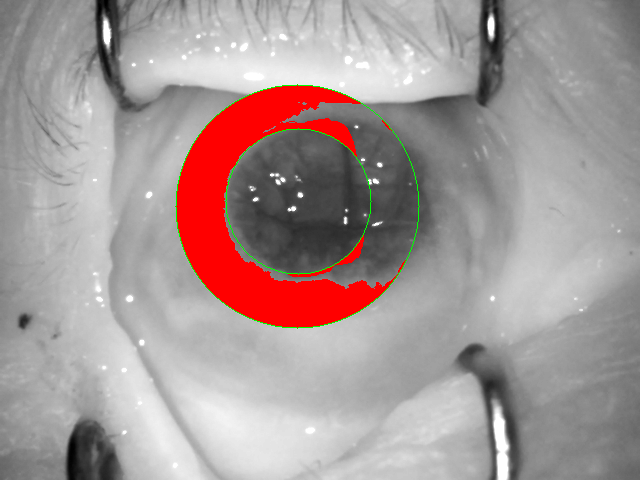

Figure 7 presents the worst results obtained from OSIRIS prior to applying score normalization. Incorrect segmentation explains the reason for a false non-match obtained for the left pair of samples. The right pair and the segmentation results show a very interesting case of a false match. Even with incorrect segmentation, as observed in this case, we still have some ‘non-occluded’ image areas that are significantly different (part of the skin on the first image and part of the wrinkled iris/cornea on the second image). So why the false match is observed? The reason for that may be a very small number of bits being compared due to application of occlusion mask during calculation of the Hamming distance. Note that the occlusions found by the OSIRIS in this image pair are almost mutually exclusive: ‘non-occluded’ part is mostly located on the left part of the hypothetical iris on the first image, while ‘non-occluded’ part of the iris shown on the second image is located mostly on the right. This false match does not happen after applying score normalization that penalizes low numbers of mutually un-occluded bits in OSIRIS codes.